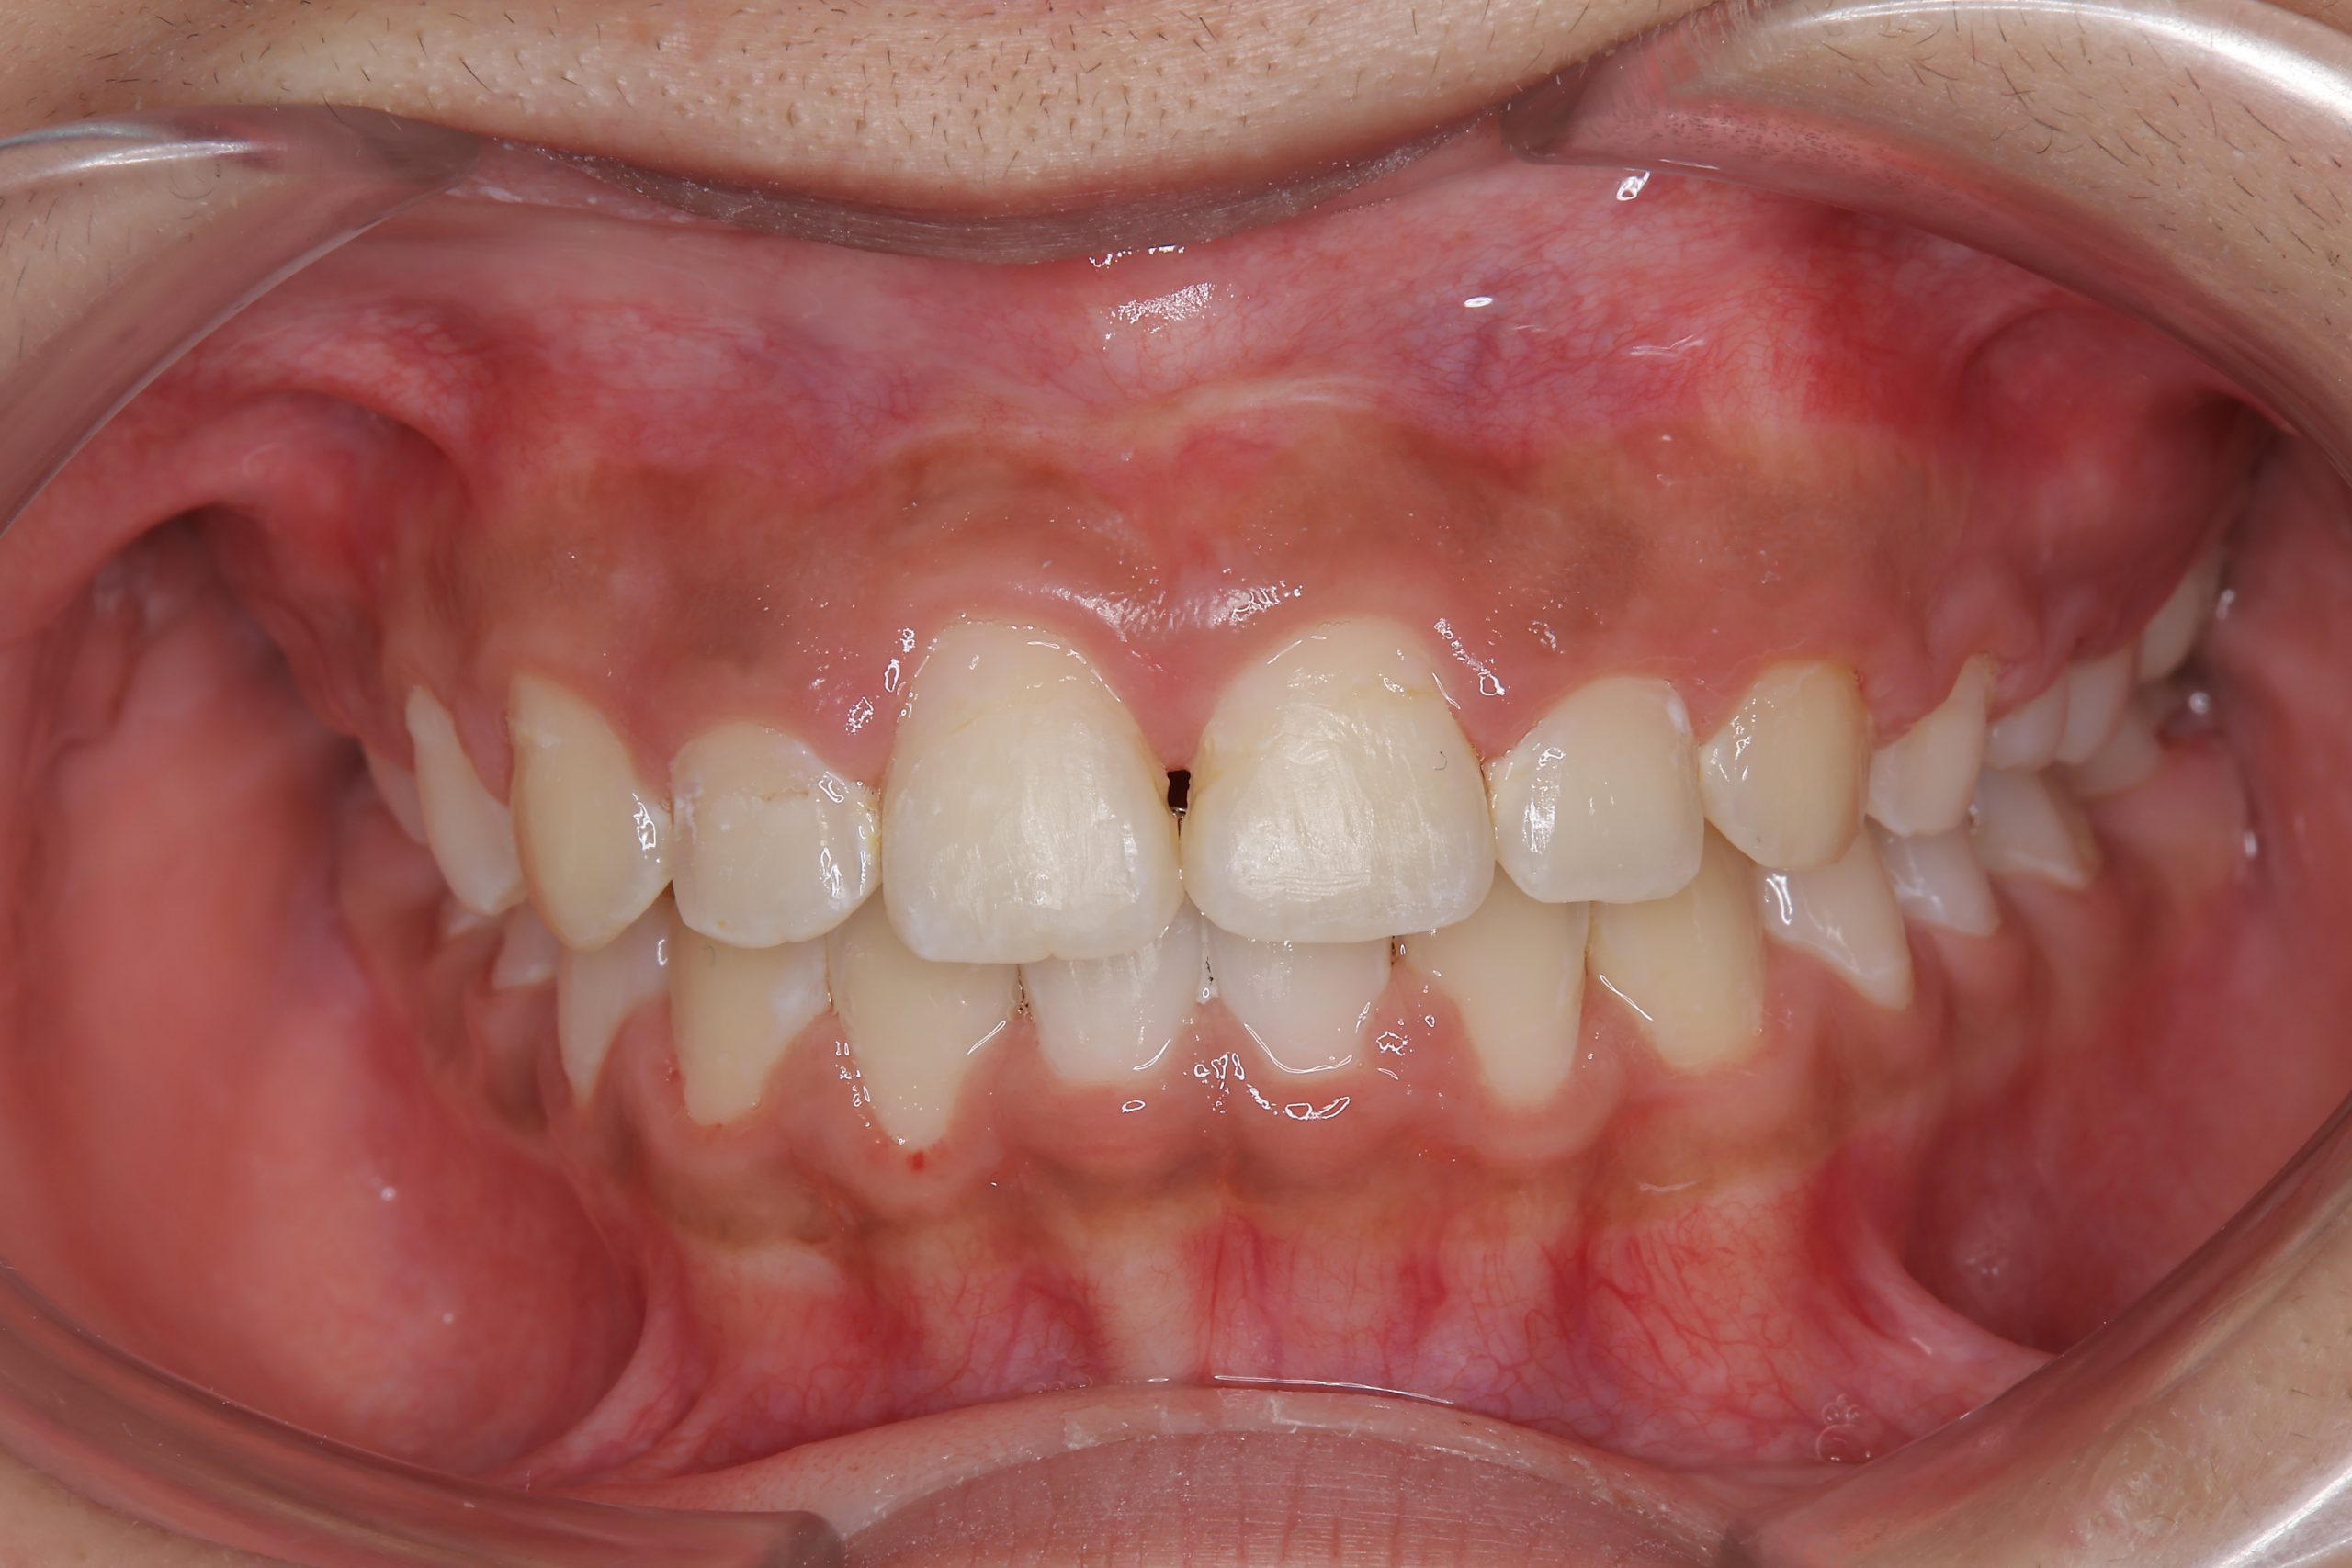

ビフォー

全顎ワイヤー矯正 症例_474

主訴 歯並びがガタガタで前歯が出ている

施術内容 小児矯正1期治療

治癒期間 1年5か月間

費用 1,020,800円(税込)